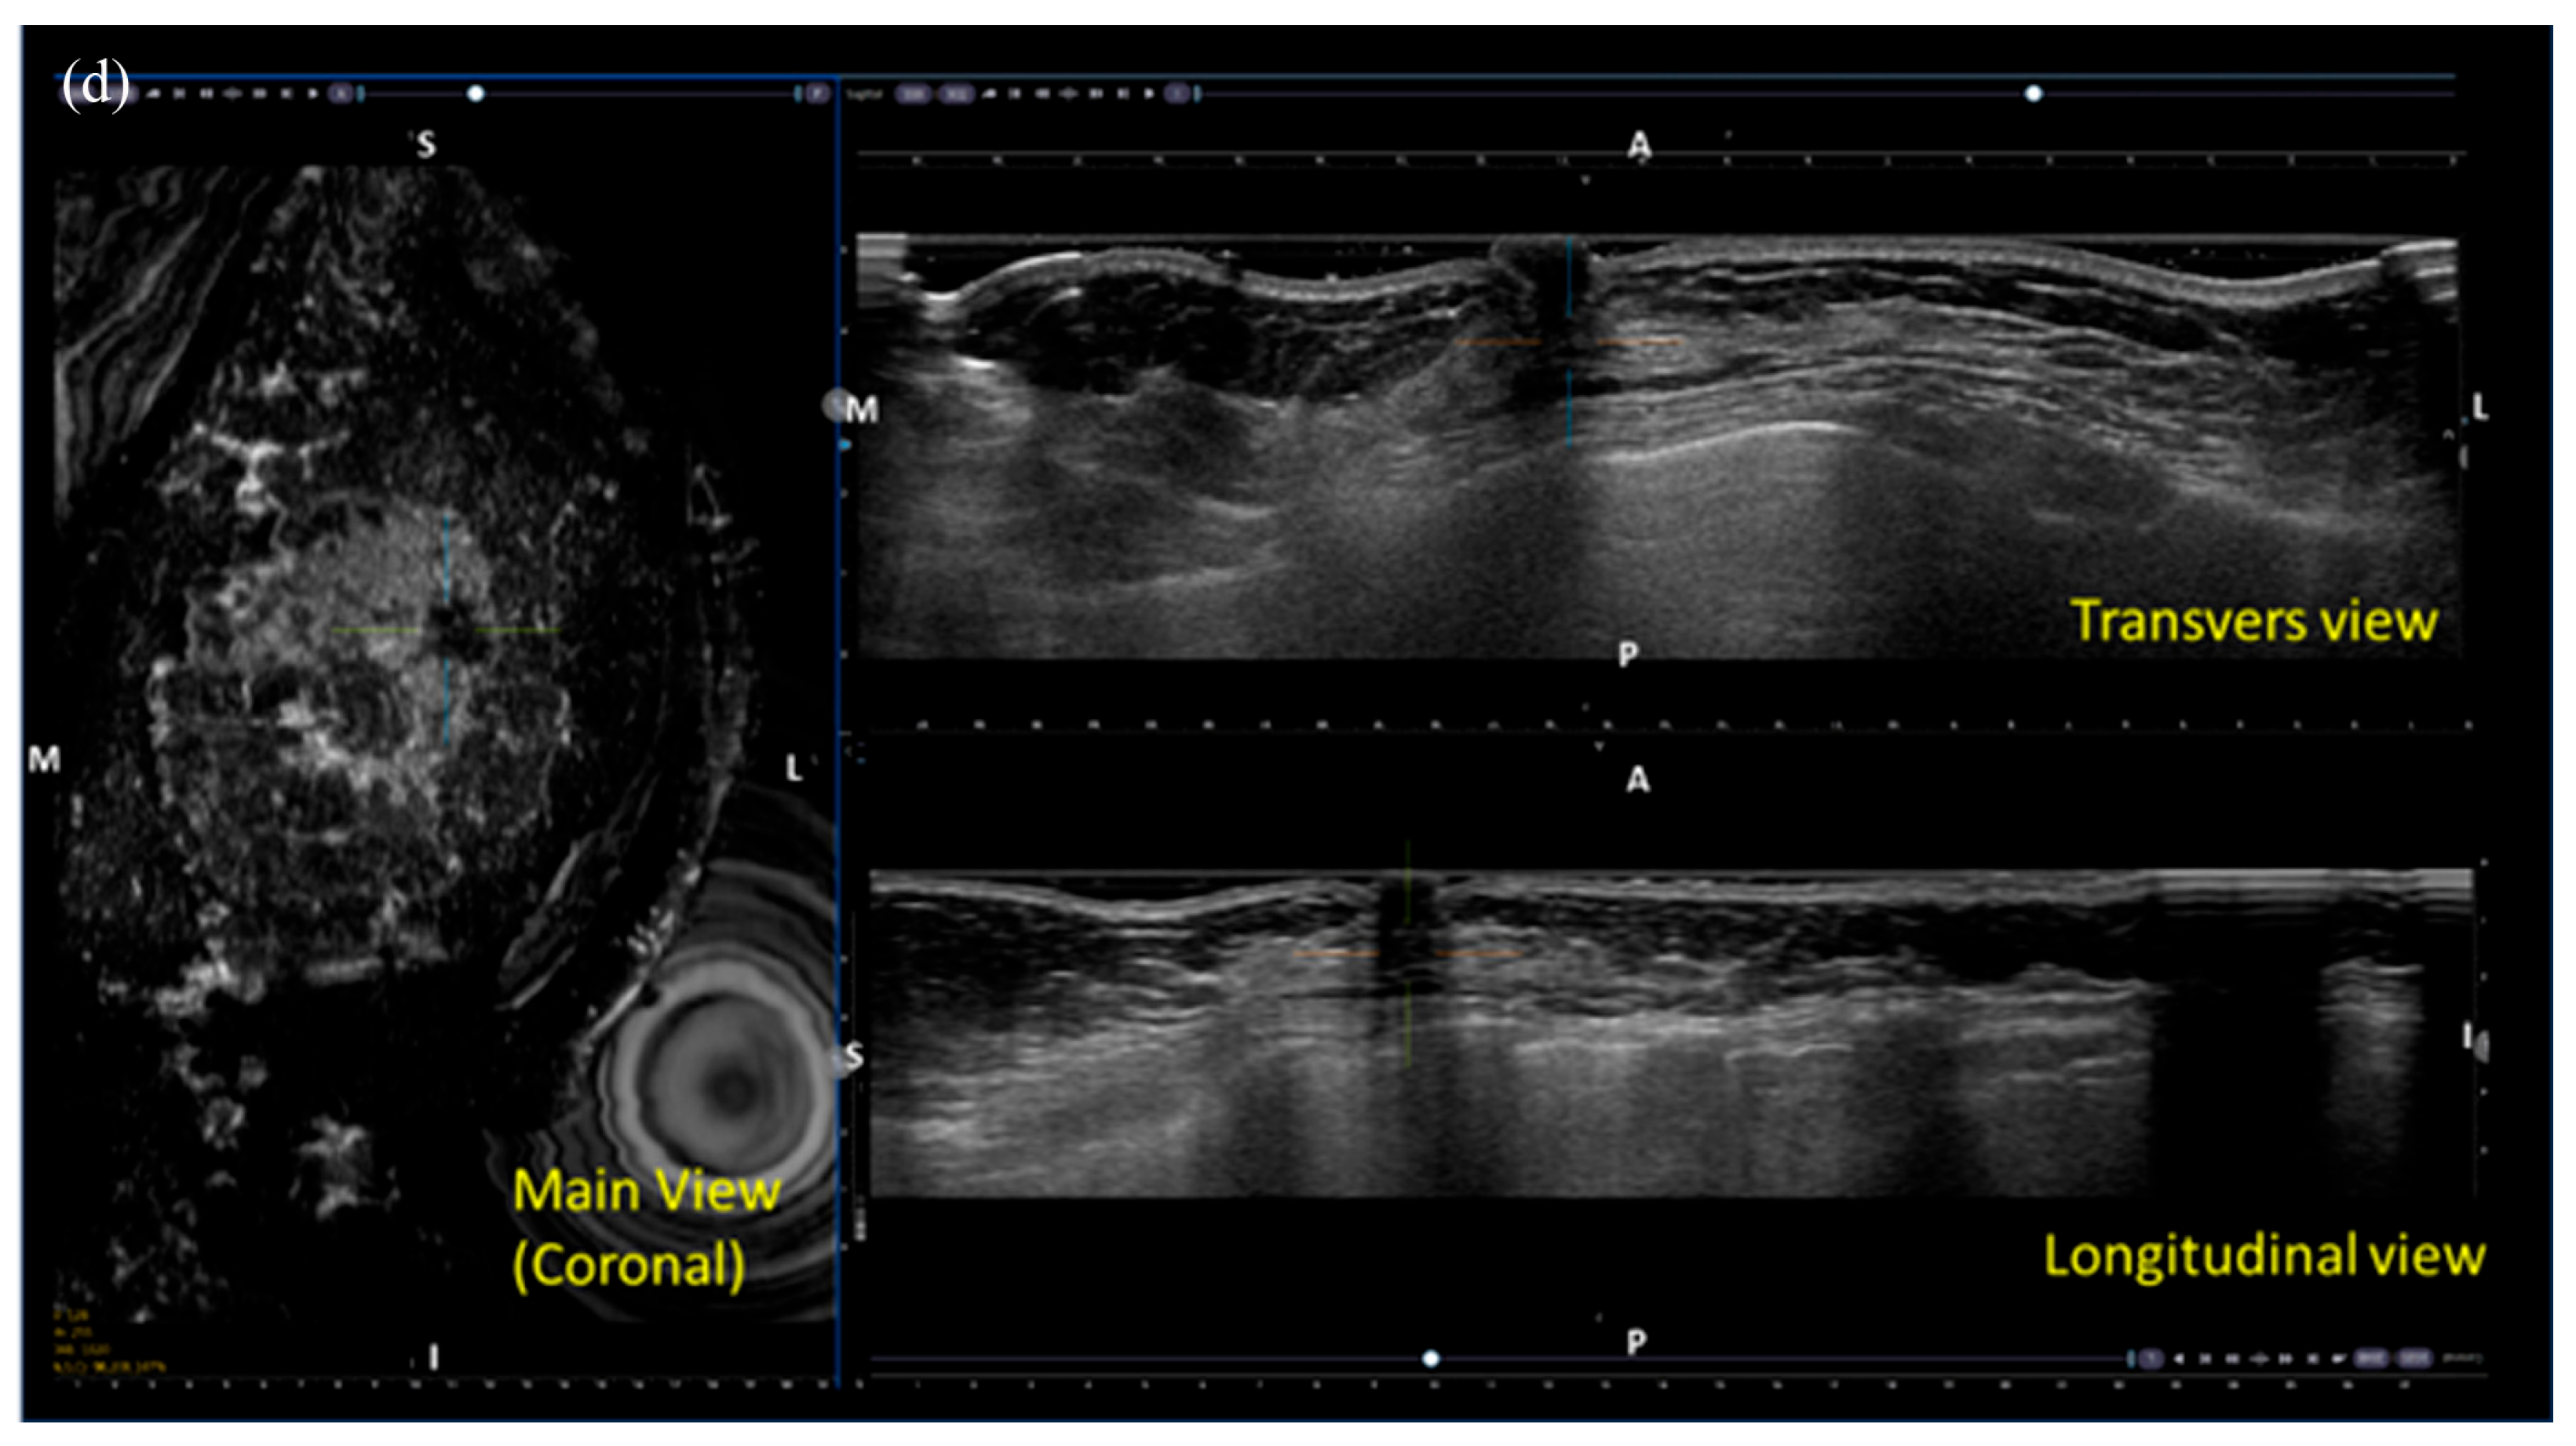

Table 5 summarizes the factors influencing lesion visibility on DBT and MammouS-N images. Lesions that were better visualized on MammouS-N included masses obscured on DBT and non-calcified lesions (p ≤ 0.005) (Figure 4 and Figure 5). Reviewer 2’s assessment showed that larger lesions tended to be better visualized using DBT. No significant associations were observed between lesion visibility and factors such as patient age, mammographic density, lesion size on MammouS-N, echotexture, or lesion type (Figure 6).

Figure 4. A 66-year-old female patient with screen-detected invasive lobular and ductal carcinoma: (a,b) The malignancy is not visualized on digital breast tomosynthesis (DBT). (c) Hand-held ultrasound reveals a spiculated, irregular, heterogeneous hypoechoic mass (arrows) in the left 12 o’clock area. (d,e) MammouS-N transverse images in craniocaudal (d) and mediolateral oblique (e) views demonstrate an indistinct, irregular, heterogeneous hypoechoic mass (arrows) in the central upper area of the left breast. S = superior, I = inferior, and M = medial.